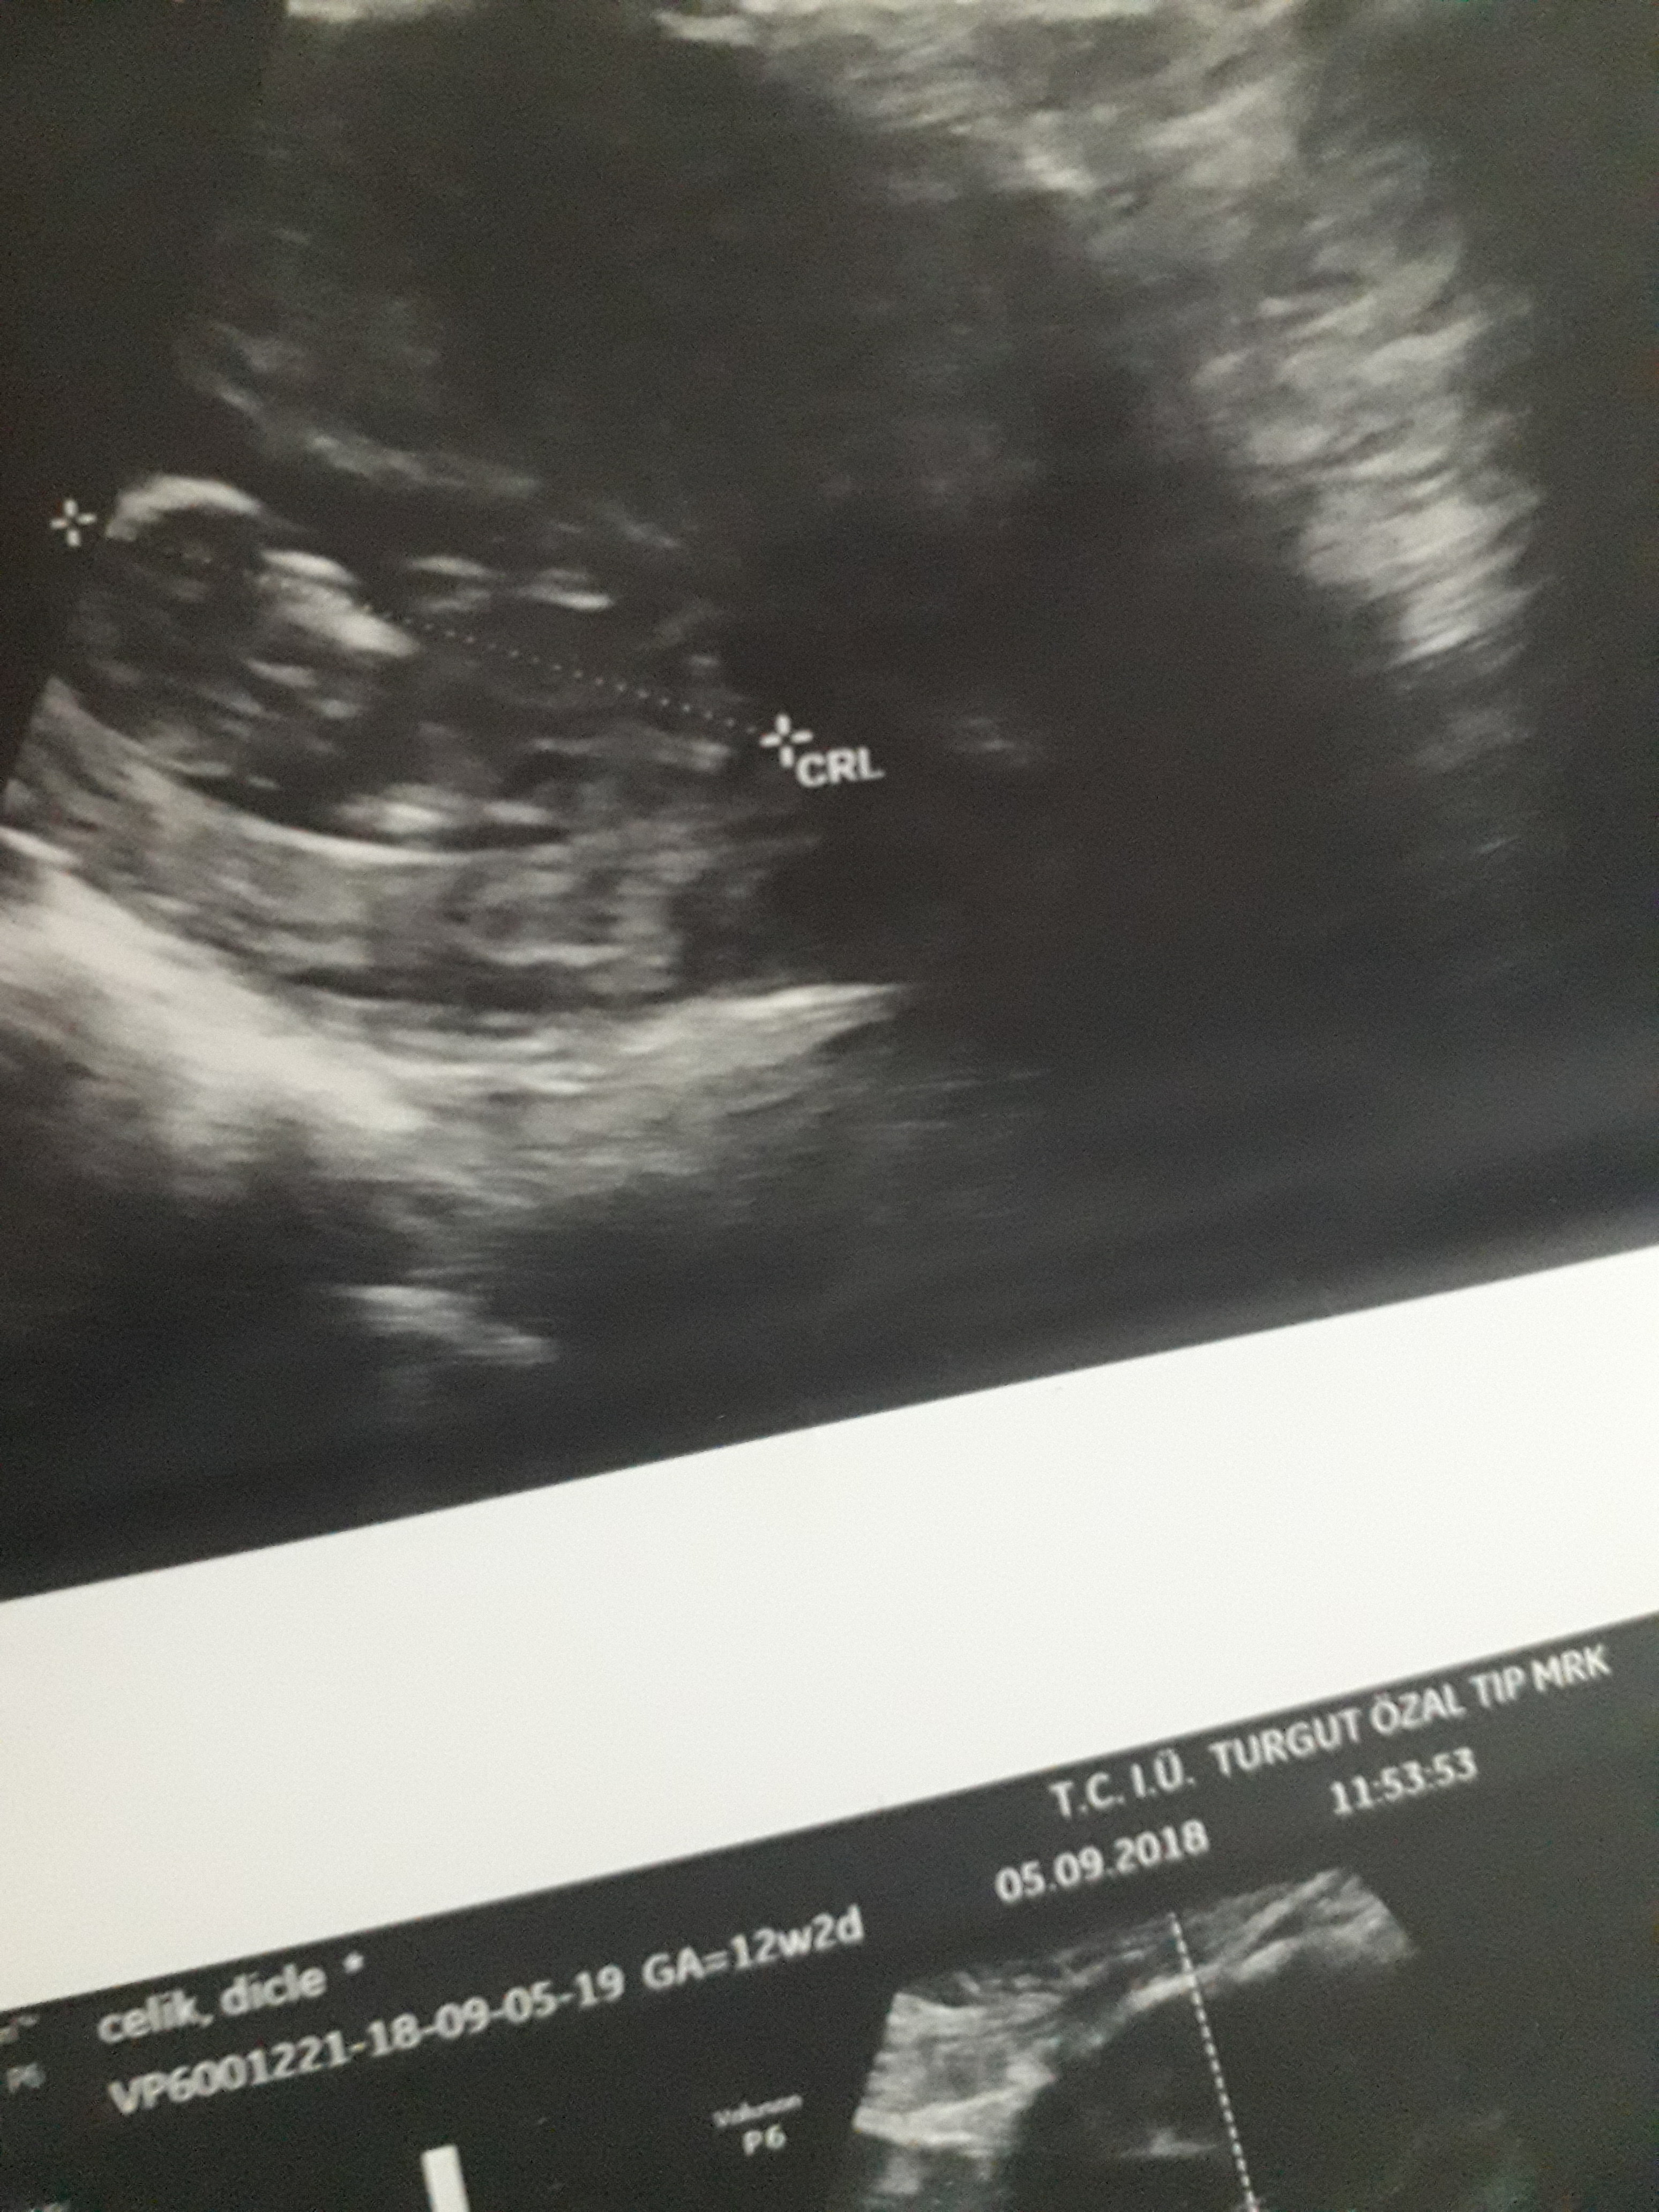

Dun malatyada verildi 12 +4 gunluk lutfen yorumlayin

Dun verildi 12 haftalik lutfen yorumlayin

Görsellerde nub çıkıntısı belli değil . Ultrasonu yapan doktor cinsiyeti hakkında bilgi vermiştir mutlaka ama şunu belirtmeden geçmeyeyim. Bu haftalarda cinsiyet tahmininde yanılma payı çok yüksek 17-19 ve 20 ci haftalarda bebeğin cinsiyetini net olarak öğrenebilirsiniz.